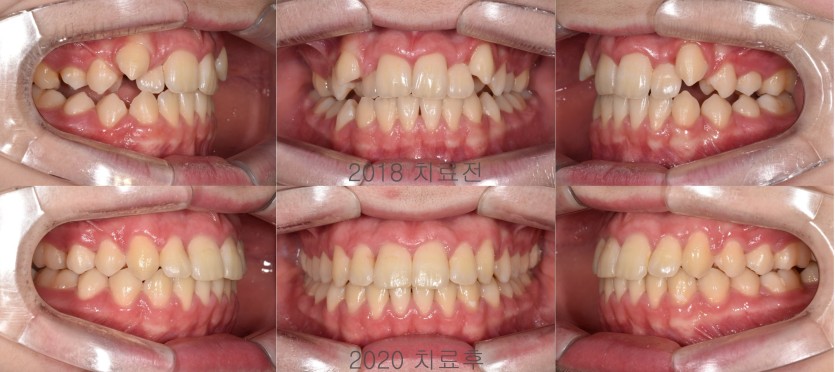

덧니의 비발치 확장 교정치료 146회

덧니가 있다고 무조건 발치 교정치료로 해결하는 것은 아닙니다 .

안모, 공간부족양, 치조골의 크기와 형태 등 다양한 요소를 고려하여 비발치 교정치료로 진행하는 경우도 많습니다.

그리고 비발치 교정치료를 진행했을 때 사용할 수 있는 장치의 종류도 다양합니다.

이 환자의 경우에는 Quadhelix 라는 완속 확장 장치를 이용하여 천천히 치열궁을 배열하였으며 그 결과는 장기간동안 잘 유지되고 있습니다.